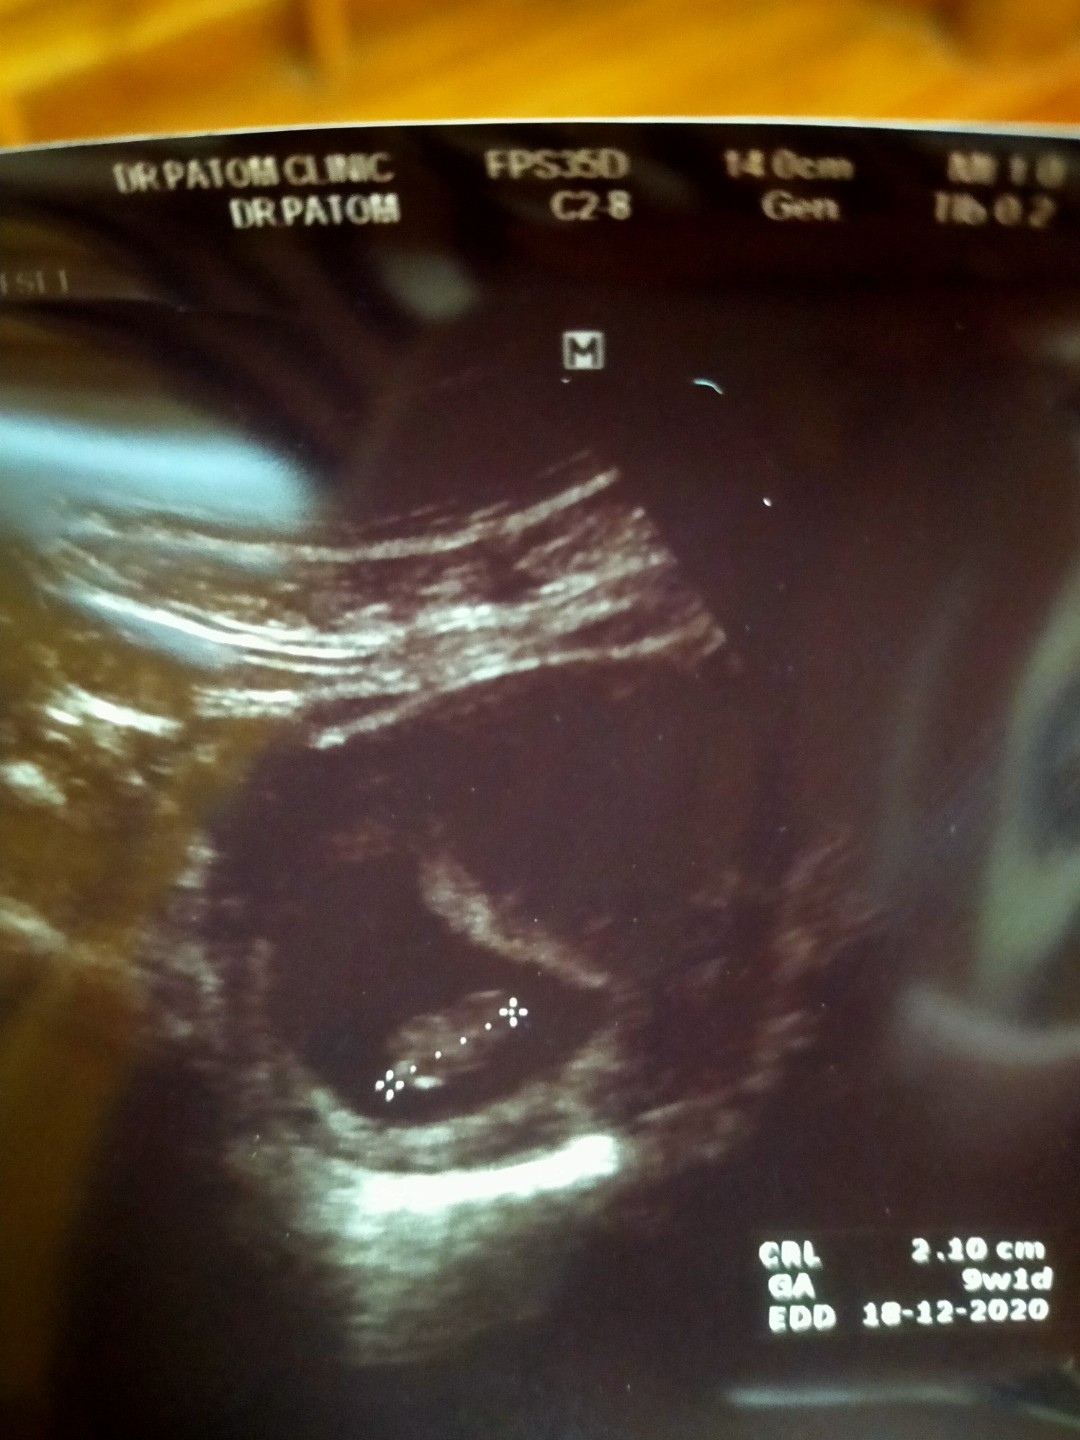

18ธันวาจ้า

16 ธ.ค 63 ค่ะ